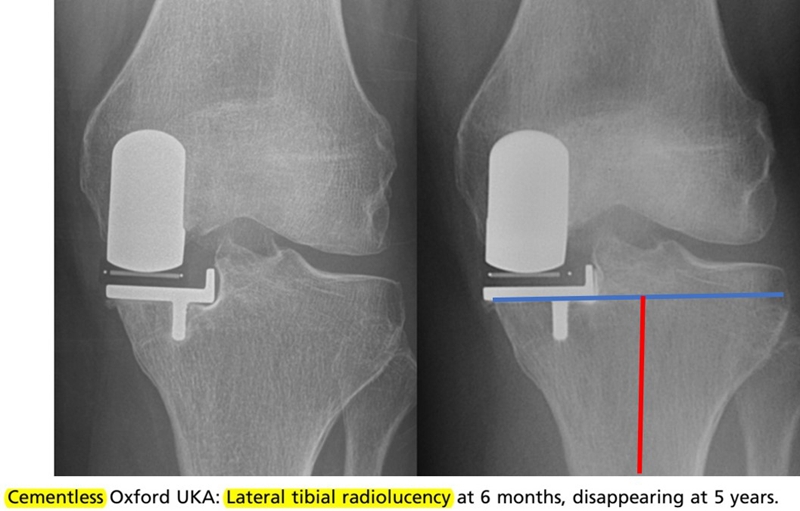

胫骨水平截骨冠状面截骨角度:0-3°,截的垂直于胫骨解剖轴线,0-3°的内翻是合适的。

避免外翻截骨

胫骨水平截骨矢状面截骨角度:胫骨截骨-7°后倾,探针(勺状测量器)贴紧股骨后方。导向器的位置近端紧贴胫骨皮质,切忌贴在骨赘上,远端一横指的位置,导向器的杆和胫骨前嵴平行。

胫骨水平截骨深度:根据胫骨假体整体厚度决定,尽量少切胫骨,MCL松弛时减少切骨量。张力是绷紧MCL即可。

冠状面对线:单髁术后冠状位对线不是由股骨假体和胫骨假体放置的内外翻决定的,而是由垫片厚度和紧张度决定的。选择可以恢复韧带张力的衬垫厚度,将下肢力线情况恢复到疾病前状态。